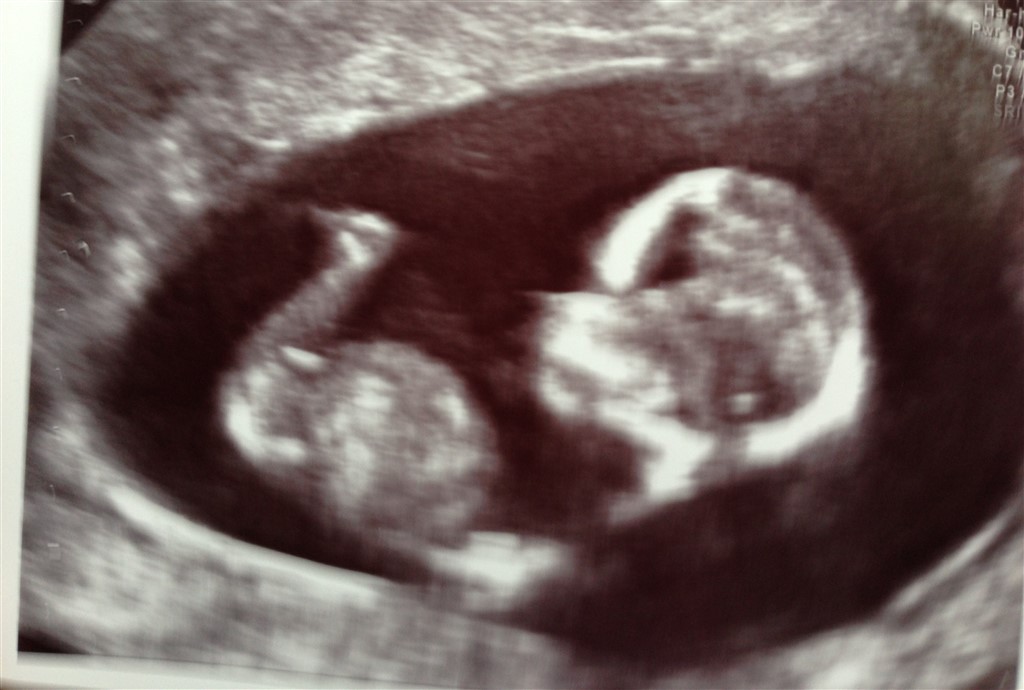

Halløj! Vi har lige været til NF scanning - alt så perfekt ud og vi fik meget lave risikovurderinger. Så alt godt so far :-) Så er næste spørgsmål jo, hvilket køn vores lille vidunder har - jeg overvejer MEGET at tilkøbe en kønsscanning her om et par uger, når de kan se det - men det kunne da være sjovt at høre nogle gæt; så skyd løs: er baby en dreng eller en pige?

Har to billeder mere - de er bare ikke helt så gode synes jeg - men I kan lige få dem

Gætter pige pga. Den høje pande, den runde hage og hvor der opstår streger ved kønnet, synes jeg de er vandrette.